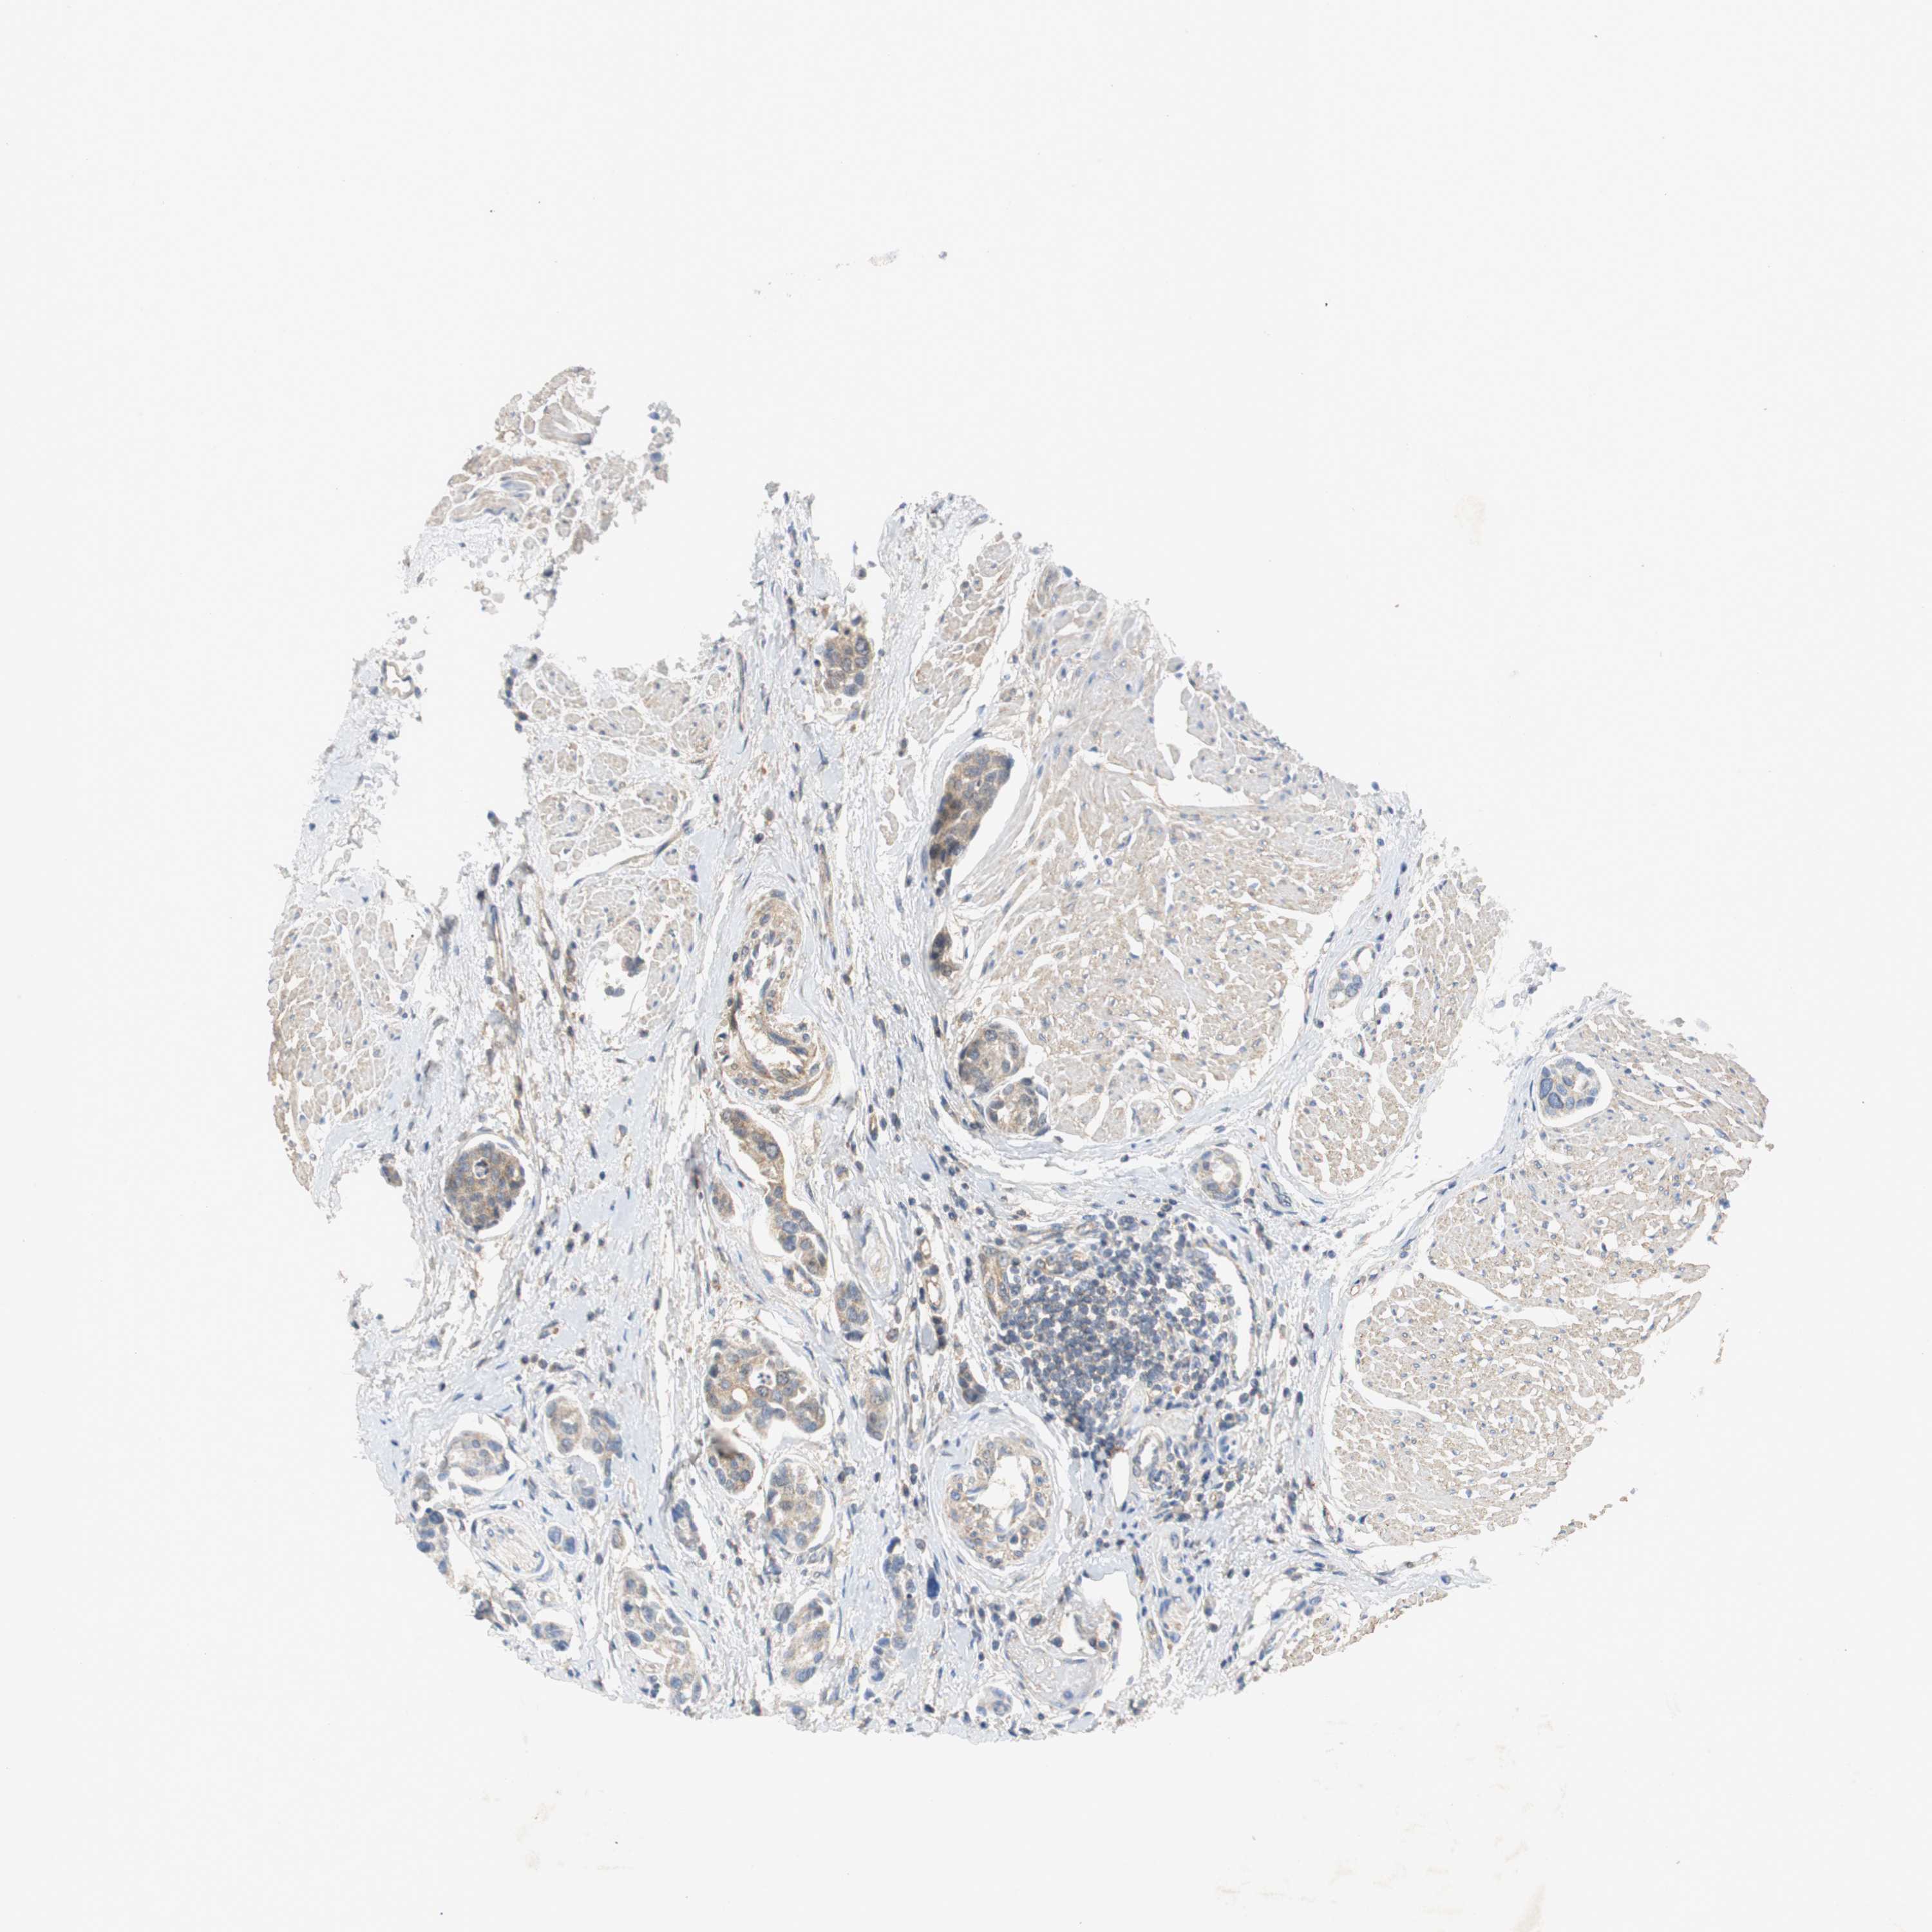

UROTHELIAL CANCER - Protein expressioni

A mouse-over function shows sample information and annotation data. Click on an image to view it in a full screen mode. Samples can be filtered based on level of antibody staining by selecting one or several of the following categories: high, medium, low and not detected. The assay and annotation is described here.

Note that samples used for immunohistochemistry by the Human Protein Atlas do not correspond to samples in the TCGA dataset.

Antibody stainingi

Antibody staining in the annotated cell types in the current human tissue is reported as not detected, low, medium, or high, based on conventional immunohistochemistry profiling in selected tissues. This score is based on the combination of the staining intensity and fraction of stained cells.

Each image is clickable and will lead to virtual microscopy that enables deeper exploration of all samples and also displays staining intensity scores, fraction scores and subcellular localization as well as patient and tissue information for each sample.

Antibody HPA023230

Antibody CAB006260

Urothelial carcinoma, Low grade

Urothelial carcinoma, High grade